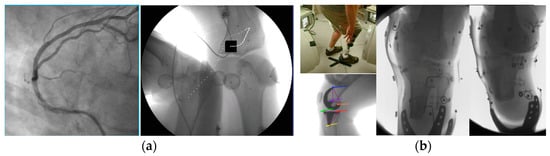

| 2D radiography (see Figure 5, Figure 6, Figure 11 and Figure 16) | See detector a, b, c resolution | 1 s to 2 min/1–360 | ~50/50/50 | SID 50–1100/ everything else is variable |

| 3D dynamic imaging stereovideography (Figure 5, Figure 6 and Figure 9) | 20–200 μm Static or moving image intensifiers with high-speed cameras | 1 s, as required by IR/10–10000 | 0.02–1.1 mSv min−1/0.08–0.9 mSv min−1/0.02–0.08 mSv min−1 | 50–1100 /10–500/variable VD and VH/0.02–0.2 |